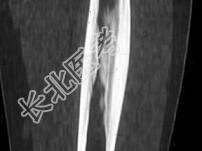

- 单项选择题青少年患者,腿痛, 如图所示,最可能诊断为 ( )

A、骨梗死

B、骨样骨瘤

C、骨肉瘤

D、骨软骨瘤

E、以上都不是